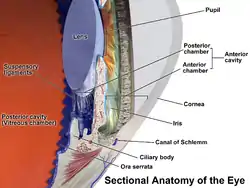

Anatomy of the anterior part of the human eye. "Suspensory ligaments" are labeled at left. | |

The zonule of Zinn (/ˈtsɪn/) (Zinn's membrane, ciliary zonule) (after Johann Gottfried Zinn) is a ring of fibrous strands forming a zonule (little band) that connects the ciliary body with the crystalline lens of the eye.[1] These fibers are sometimes collectively referred to as the suspensory ligaments of the lens, as they act like suspensory ligaments.

The zonule of Zinn is split into two layers: a thin layer, which lies near the hyaloid fossa, and a thicker layer, which is a collection of zonular fibers. Together, the fibers are known as the suspensory ligament of the lens.[4] The zonules are about 1–2 μm in diameter.[5]

The zonules attach to the lens capsule 2 mm anterior and 1 mm posterior to the equator, and arise of the ciliary epithelium from the pars plana region as well as from the valleys between the ciliary processes in the pars plicata.[6][7]